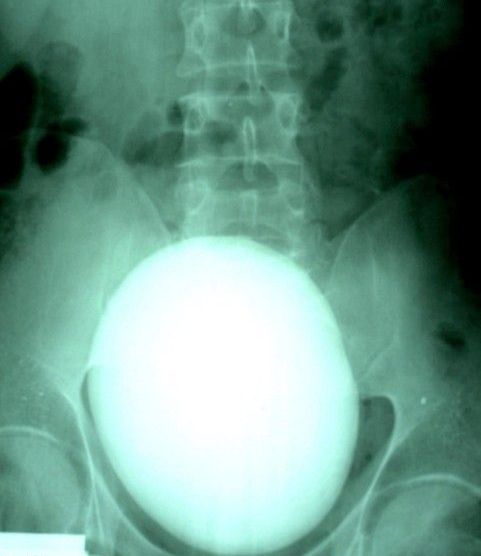

It is horrible to imagine that such thing can be inside of a human body.

It is even more horrible to imagine how it can be extracted from there.

Here’s the story of one kidney stone which weighs only 1 kilogram after the jump.